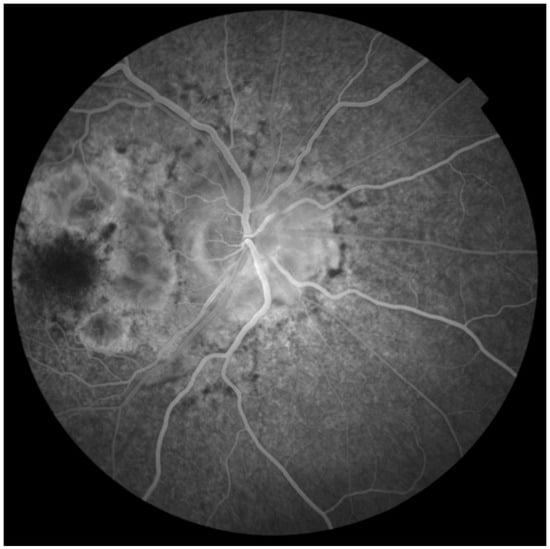

2. Case Report

Investigations and Results